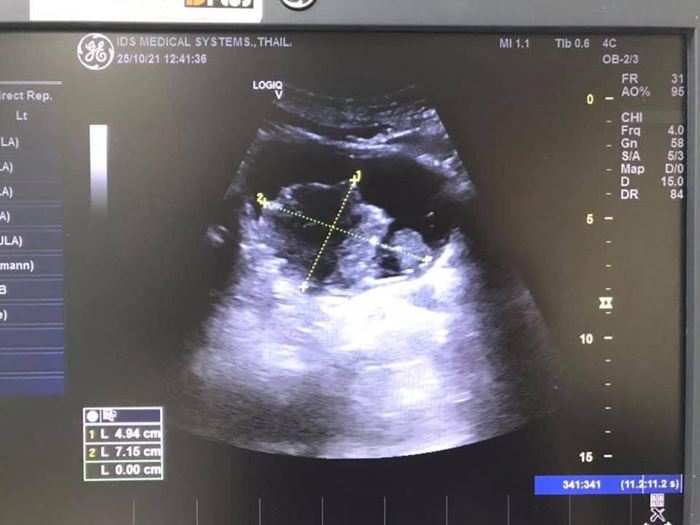

เลยเอาอัลตราซาวด์มาตรวจดู เมื่อได้เห็นภาพจากหน้าจออัลตราซาวด์ ก็ต้องตกใจ พร้อมกับต้องหันไปทวนดูอายุคนไข้อีกทีว่าดูตัวเลขผิดไปหรือเปล่า เพราะเป็นไปอย่างที่แอบคิดไว้ในใจลึก ๆ (แต่ไม่อยากให้เป็นจริง) ตั้งแต่แรกจริง ๆ ด้วย มันคือ "ก้อนเนื้องอก (มะเร็ง) ก้อนใหญ่เกือบ 10 เซนติเมตรในกระเพาะปัสสาวะ